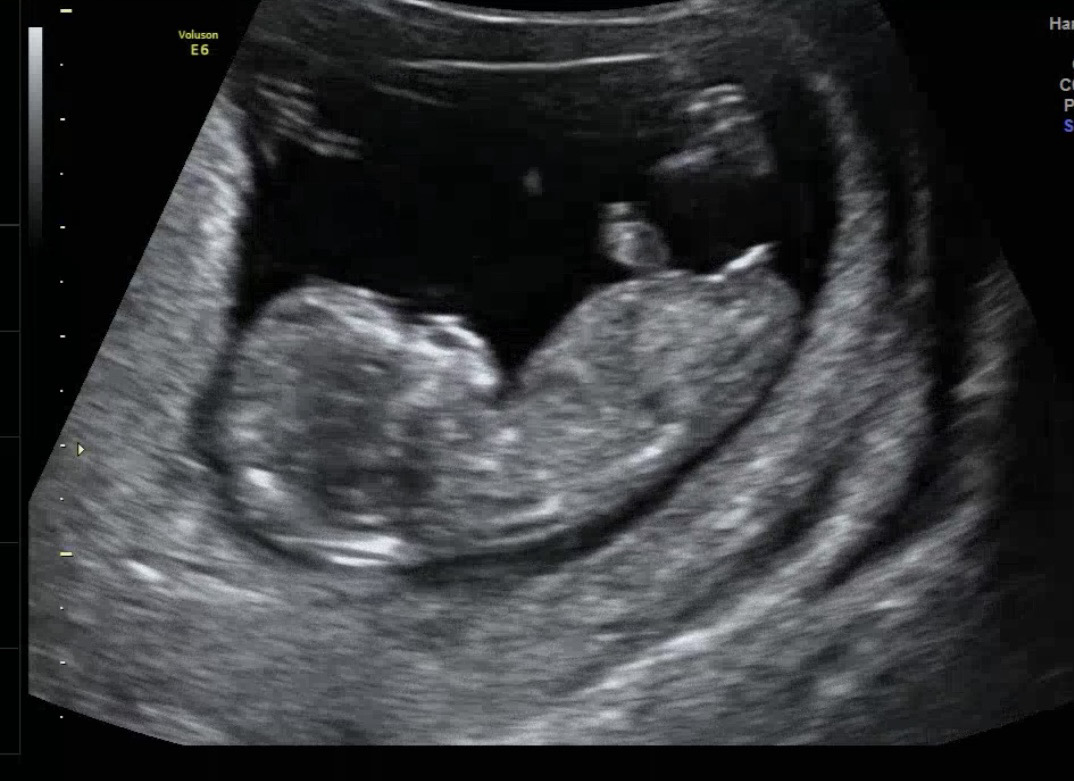

11주차 초음파 아들 VS 딸

아직 이르지만 한번 봐주세요 🤍🤍